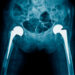

Jei kiti metodai nebeveiksmingi, taikoma operacija – dažniausiai tai klubo keitimas. Operacijos būna dviejų pagrindinių tipų:

- Klubo paviršiaus atkūrimas (resurfacing): pašalinama pažeista kremzlė ir kaulo paviršius, o vietoje jų įstatomos specialios metalinės dangos, užtikrinančios sklandų judėjimą.

- Pilnas klubo keitimas: pažeistos dalys pakeičiamos dirbtinėmis (protezais), kurie tarnauja ne vieną dešimtmetį.